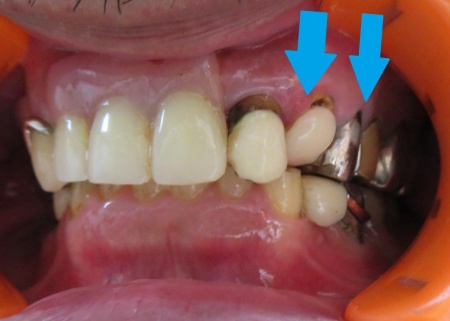

カウンセリング・診断結果 拝見したところ、左上の歯が折れて歯根だけが残っている状態でした。

これが原因で、入れ歯を固定する金属のバネ「クラスプ」をかける歯の土台が失われ、入れ歯が安定しなくなっています。